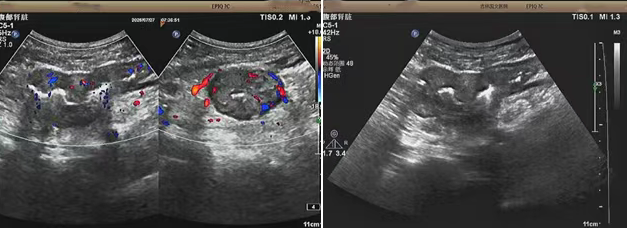

超聲檢查的結(jié)果進(jìn)一步揭示了病情的細(xì)節(jié):下腹部偏左腸壁顯著增厚,原本清晰的層次結(jié)構(gòu)遭到破壞,周?chē)鹃g隙變得模糊,網(wǎng)膜回聲也出現(xiàn)增強(qiáng)的現(xiàn)象,同時(shí),腸腔狹窄的情況也得到了確認(rèn)。經(jīng)過(guò)完善的檢查,最終將病變精準(zhǔn)定位在乙狀結(jié)腸 - 直腸交界區(qū),并且對(duì)病變范圍及周?chē)?rùn)情況做出了評(píng)估,這些關(guān)鍵信息為后續(xù)的診療工作提供了重要依據(jù),讓醫(yī)生們能更有針對(duì)性地制定治療方案。

我院超聲檢查在此次診療過(guò)程中展現(xiàn)出了顯著的技術(shù)亮點(diǎn)。一方面,它能做到 “明察秋毫”,通過(guò)高頻探頭可以清晰地顯示腸壁各層結(jié)構(gòu)的變化,為臨床判斷病變性質(zhì)提供了客觀、準(zhǔn)確的依據(jù),讓醫(yī)生能更清晰地了解腸道內(nèi)部的病變狀態(tài)。另一方面,它實(shí)現(xiàn)了 “精準(zhǔn)評(píng)估”,不僅準(zhǔn)確找到了病變的位置,還能全面評(píng)估病變對(duì)周?chē)M織的影響,這對(duì)于協(xié)助醫(yī)生制定科學(xué)合理的治療方案起到了至關(guān)重要的作用,有助于提高治療的有效性和安全性。